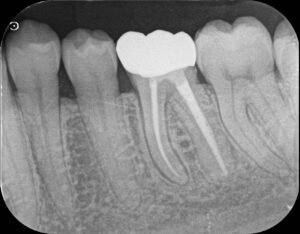

「抜髄」は“Initial Treatment”と言われ、神経の治療がされていない歯の治療(初回の治療↓)になります。

→